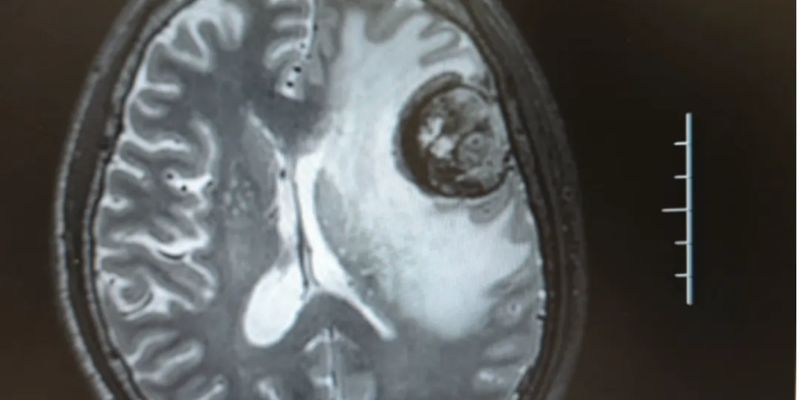

本文通过一例局限期小细胞肺癌(SCLC)脑转移患者的成功治疗案例,深入探讨了替尼泊苷联合伊立替康及恩沃利单抗方案的显著疗效。了解该方案如何有效缩小脑部肿瘤,为SCLC脑转移治疗带来新希望,并探索替尼泊苷的价格与购买渠道。 Read More... "替尼泊苷治疗小细胞肺癌脑转移效果如何?真实病例揭示新希望"

本文分享一例晚期转移性肺大细胞神经内分泌癌(LCNEC)患者的成功治疗案例。该患者存在脑转移,在使用替尼泊苷联合卡铂等药物化疗后,肺部和脑部病灶均明显缩小,达到部分缓解(PR)。了解替尼泊苷在治疗LCNEC脑转移中的显著疗效、安全性和潜在的生存获益。想知道替尼泊苷的价格和购买渠道吗?点击查看详情。 Read More... "替尼泊苷治疗肺大细胞神经内分泌癌脑转移效果显著:一例成功病例深度解析"